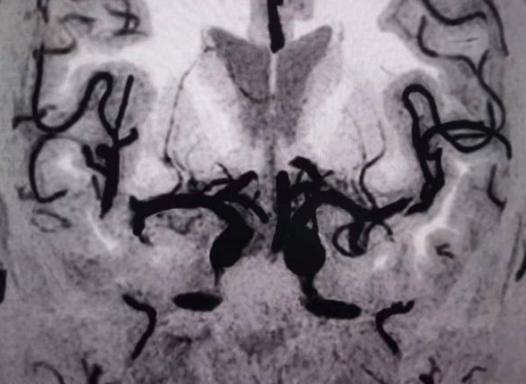

6招丨高危人群的健康(斑块)筛查

d8e1111fe9b857db9a5263342f3650d9.png75171507dca801d3d22214fa0a34ddd3.png

4962a5d190b6d4070e46a59d830b7b26.pnge091ebb0ad3daa65bcf1e30a69dba791.png

通过观察大脑深部穿支动脉如豆纹动脉、内囊动脉开口及管腔情况,可以早期预测发生腔隙性脑梗塞事件的风险。